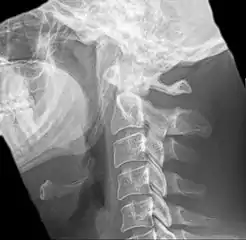

| Anteroposterior and lateral radiographs of cervical spine showing ossification of the stylohyoid ligament on both sides | |

Eagle syndrome (also termed stylohyoid syndrome,[1] styloid syndrome,[2] styloid-stylohyoid syndrome,[2] or styloid–carotid artery syndrome)[3] is an uncommon condition commonly characterized but not limited to sudden, sharp nerve-like pain in the jaw bone and joint, back of the throat, and base of the tongue, triggered by swallowing, moving the jaw, or turning the neck.[1] First described by American otorhinolaryngologist Watt Weems Eagle in 1937,[4] the condition is caused by an elongated or misshapen styloid process (the slender, pointed piece of bone just below the ear) and/or calcification of the stylohyoid ligament, either of which interferes with the functioning of neighboring regions in the body, such as the glossopharyngeal nerve.[4]

Eagle syndrome occurs due to elongation of the styloid process or calcification of the stylohyoid ligament, potentially compressing the nearby carotid arteryor glossopharyngeal nerve.[4] However, the cause of the elongation hasn’t been known clearly. It could occur spontaneously or could arise since birth. Usually normal stylohyoid process is 2.5–3 cm in length, if the length is longer than 3 cm, it is classified as an elongated stylohyoid process.[10] There are reports of eagles syndrome been elicited after wisdom tooth removal. [11]

Radiograph, lateral view showing elongated stylohyoid process and stylohyoid ligament ossification